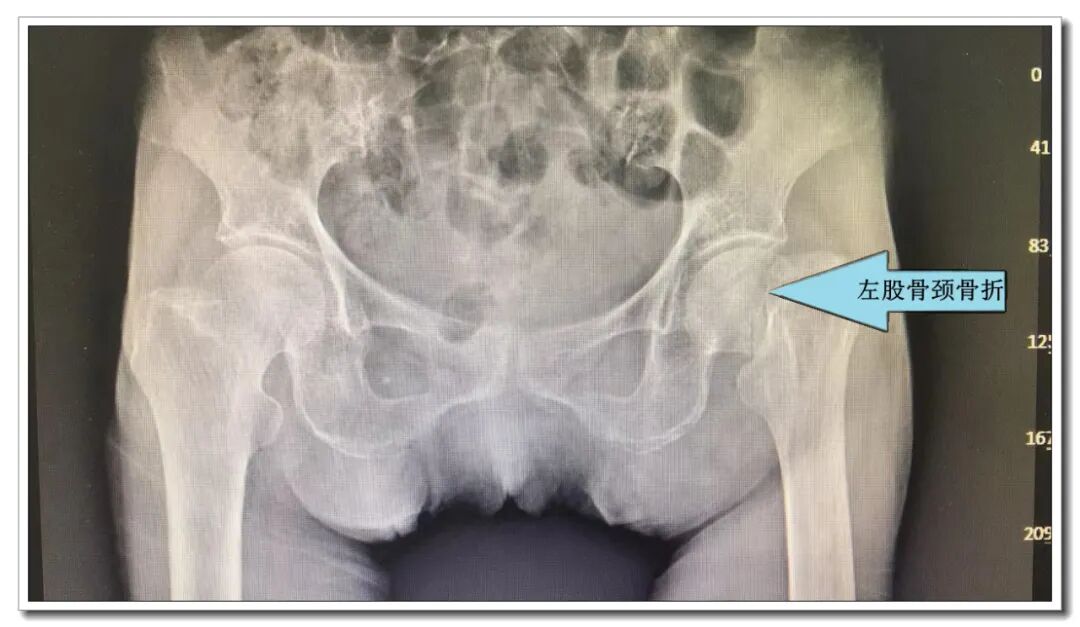

▲股骨头置换术后影像资料

在向徐阿婆及其家属详细告知阿婆的病情及治疗方案后,家属非常信任我们,毫不犹豫选择手术治疗。患者入院后,在骨外科丘均友主任医生的主持下,麻醉科团队,重症学科团队会诊意见经科室充分、认真、细致的术前讨论和术前准备,由骨外科丘均友主任医师主刀,经验丰富的麻醉师和护士负责术中配合,阿婆的手术用时30分钟顺利完成。术后在骨外科护理团队、康复医生的精细护理、康复指导下,徐阿婆术后第一天便可下地行走,术后2周顺利康复出院。出院时徐阿婆和家属均露出了开心的笑脸。